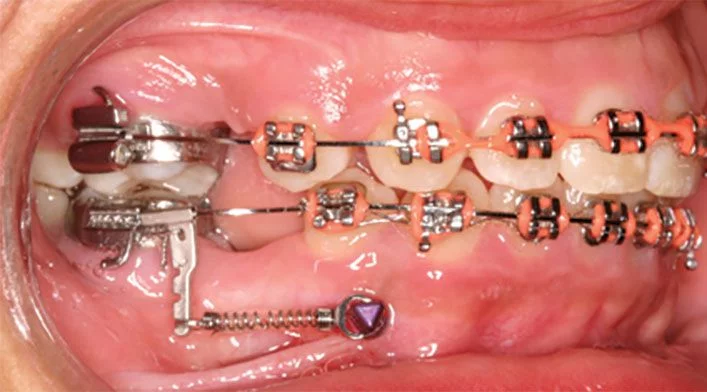

TAD mini-screws for dental asymmetries and protraction

Dental and Facial Asymmetries

Misalignment of the dental midline or tilting of the occlusal plane. TADs correct the plane and reposition the teeth relative to the face.

TAD mini-screws for molar distalization

Molar Distalization

Molars too far forward creating crowding. TADs push the back teeth backward, creating space without extractions.